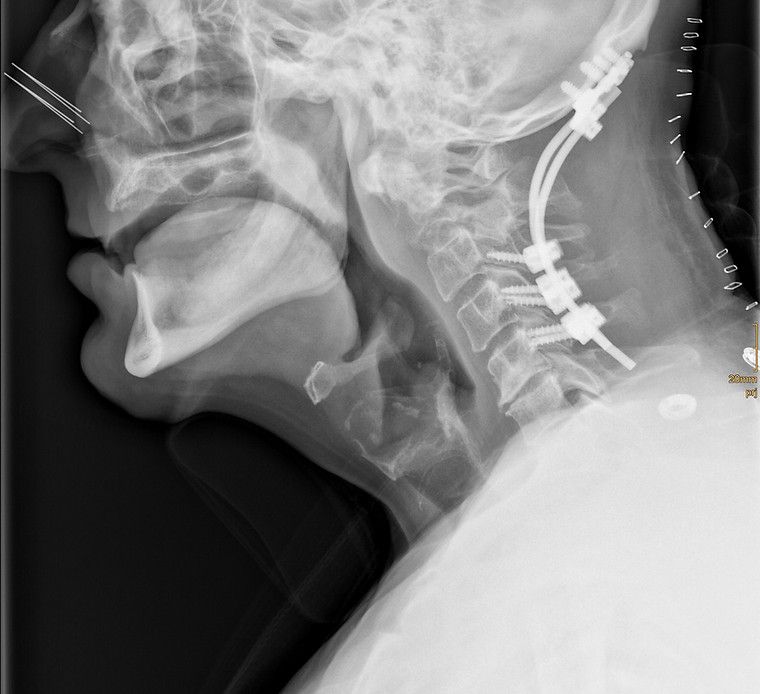

Als Facharzt für Orthopädie lag mein Schwerpunkt als Oberarzt im Wirbelsäulenteam des AKH Wien von 2019 bis 2024 auf der operativen Versorgung von Erkrankungen der Wirbelsäule. In den vergangenen Jahren habe ich viele hundert Wirbelsäulenoperationen durchgeführt – von mikrochirurgischen Eingriffen bis hin zu minimalinvasiven rekonstruktiven Verfahren. Dank meiner langjährigen Erfahrung verfüge ich über besondere Expertise in Bandscheibenoperationen, Dekompressionen sowie in der chirurgischen Behandlung schwerer Wirbelsäulenpathologien. Diese Eingriffe erfordern höchste Präzision, Sorgfalt und ein tiefes Verständnis der individuellen Krankheitsbilder. Besonders wichtig ist mir dabei, Sie umfassend zu beraten und gemeinsam mit Ihnen die für Sie beste Therapieentscheidung zu treffen. Ich nehme mir ausreichend Zeit für Ihre Fragen und sorge dafür, dass Sie sich medizinisch wie menschlich gut aufgehoben fühlen.

Rekonstruktive Wirbelsäulenchirurgie

Wirbelsäulenpathologien werden durch minimalinvasive rekonstruktive Eingriffe versorgt.